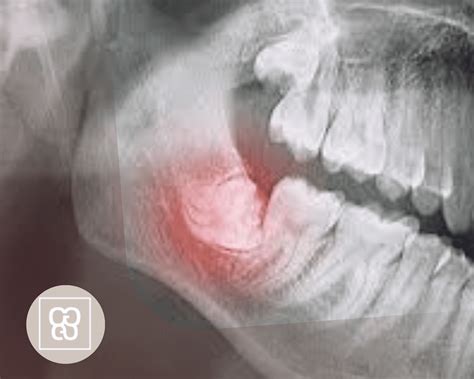

Muchas personas sufren la impactación de las muelas del juicio. A veces, estas muelas no tienen suficiente espacio para salir correctamente y se quedan parcial o totalmente retenidas en el hueso o la encía. Esto se produce cuando las muelas del juicio no tienen suficiente espacio para erupcionar en la boca o para desarrollarse normalmente. Para evitarlos, los odontólogos suelen recomendar la extracción de las muelas del juicio retenidas.

- Otro aspecto a valorar es si observas que la muela está erupcionando parcialmente y no de forma uniforme. Esto es un signo de que la muela puede quedar incluida o retenida en el interior del hueso.

Si existe la necesidad de extraer las muelas del juicio, el odontólogo valorará si el procedimiento se puede realizar en la misma consulta dental. En función del estado de la cordal, la extracción puede ser simple o con cirugía. No obstante, cuando la muela está rotada o parcialmente incluida dentro del hueso dental, hay que realizar una incisión en la encía para acceder al diente. El cirujano hace una incisión en la encía y retira el hueso que cubre la muela. Luego, extrae la muela entera o por fragmentos, y cierra la herida con puntos de sutura con mucha delicadeza.